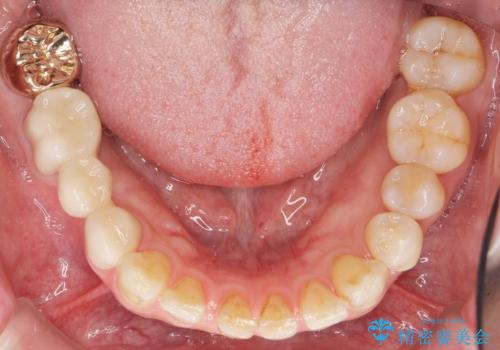

- 右下の奥歯がしみることを主訴に来院された患者様です。

精査したところ、横向きに生えた親知らずのせいで隣の歯(右下7)が虫歯になっていました。

親知らずを抜歯して隣の歯のう蝕を除去し、歯肉の治癒をしっかり待ったのち、患者様のご希望によりゴールド(PGA)クラウンによる補綴を行いました。

その後ブリッジの治療も希望され、オールセラミックのブリッジによる補綴を行いました。